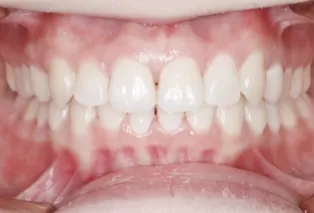

Photos intra-orales après traitement